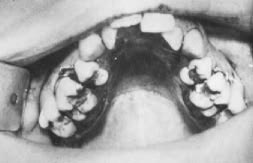

Fig. 1 The surgical procedure after completion of the median palatal osteotomy. The bone has been completely split using a surgical bur.